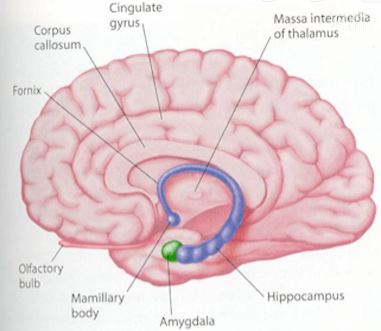

- 大脑结构图一

图1-1 - 前脑(黄色):计划、策略、情绪控制;

- 顶叶(紫色);

- 颞叶(灰色);

- 枕叶(绿色)。

- 神经细胞可以再生(但只有嗅脑和海马回可以)

管记忆的神经细胞可以再生(海马回)

- 负责记忆的地方——海马回

图7-1 - 失忆症分为